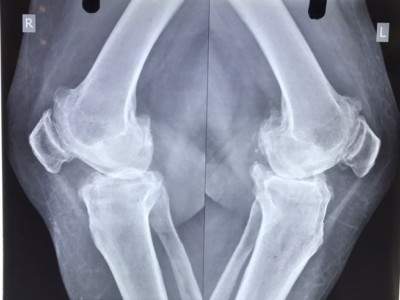

Patient Photos

PRE-OPERATIVE